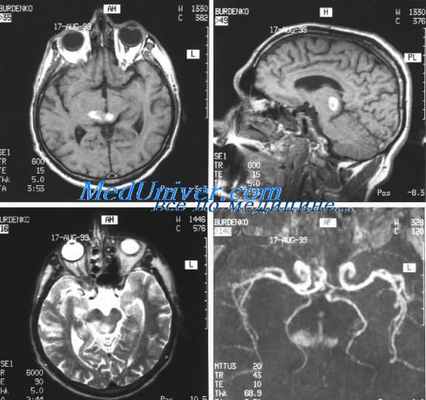

Диагностика менингита начинается с осмотра пациента и сбора анамнеза (оценка менингеальных признаков). После назначается ряд исследований, среди которых основным является люмбальная пункция. Ее проведение позволяет точно установить причину заболевания.

Также, при проведении диагностики менингита назначаются:

- микробиологический анализ ликвора;

- общий и биохимический анализ крови;

- рентгенография;

- электромиография;

- серодиагностика;

- МРТ;

- анализы на выявление возможных возбудителей;

- общий анализ мочи.

В тяжелых случаях диагностика менингита дополняется определением кислотно-щелочного баланса и анализом на свертываемость крови.